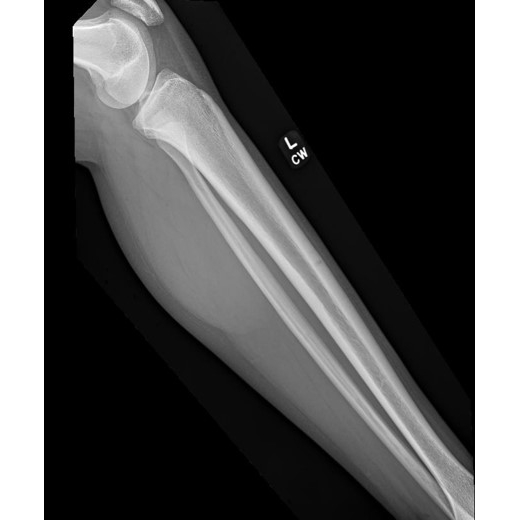

| Hoop Dreams And Bone Nightmares - Page #3 | |||